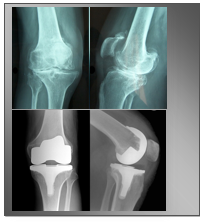

شكل خشونة النفاصل فيالاشعة

أشعة سينية لالتهاب المفاصل في الركبة Mayo Clinic مايو كلينك